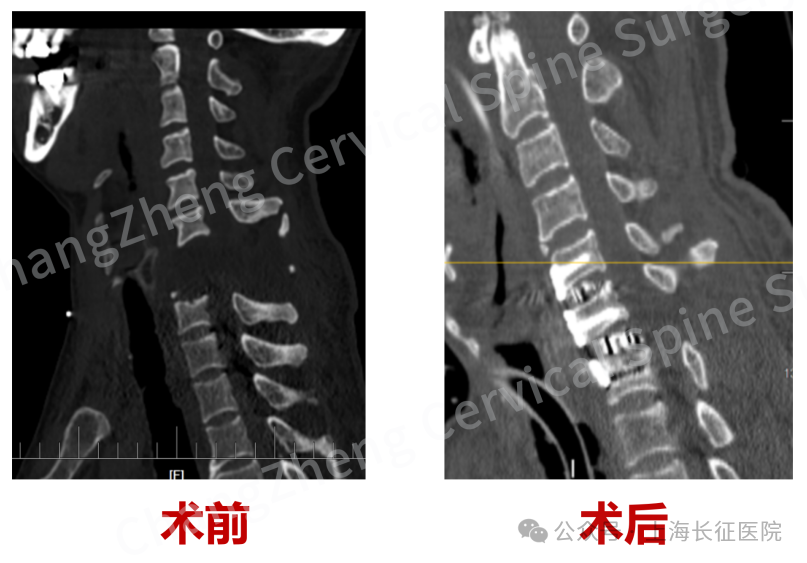

术前、术后影像对比,手术效果良好